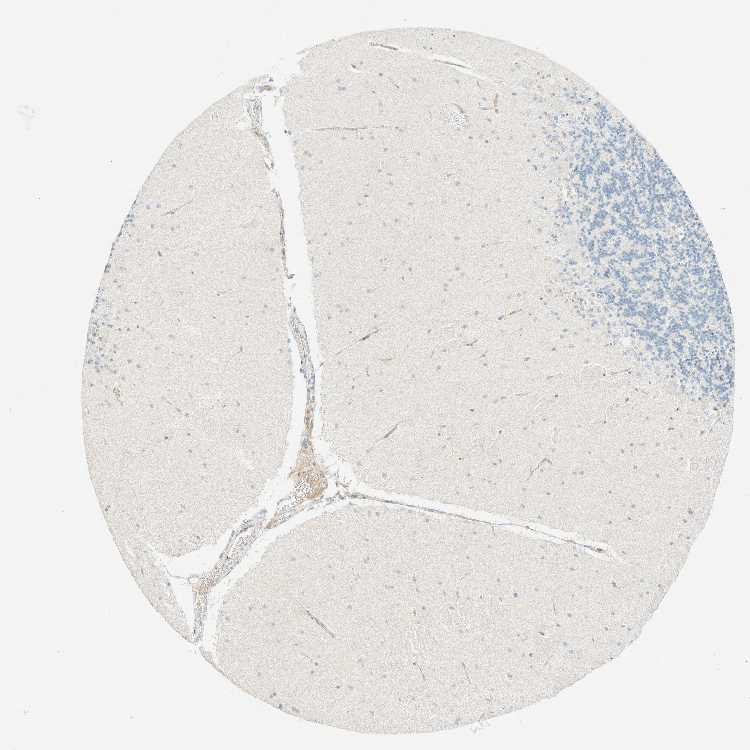

CEREBELLUM - Antibody stainingi

Antibody staining in the annotated cell types in the current human tissue is reported as not detected, low, medium, or high, based on conventional immunohistochemistry profiling in selected tissues. This score is based on the combination of the staining intensity and fraction of stained cells.

Each image is clickable and will lead to virtual microscopy that enables deeper exploration of all samples and also displays staining intensity scores, fraction scores and subcellular localization as well as patient and tissue information for each sample.

Antibody HPA018858Antibody CAB025943

Purkinje cells Not detectedNot detected

Cells in granular layer Not detectedNot detected

Cells in molecular layer Not detectedNot detected